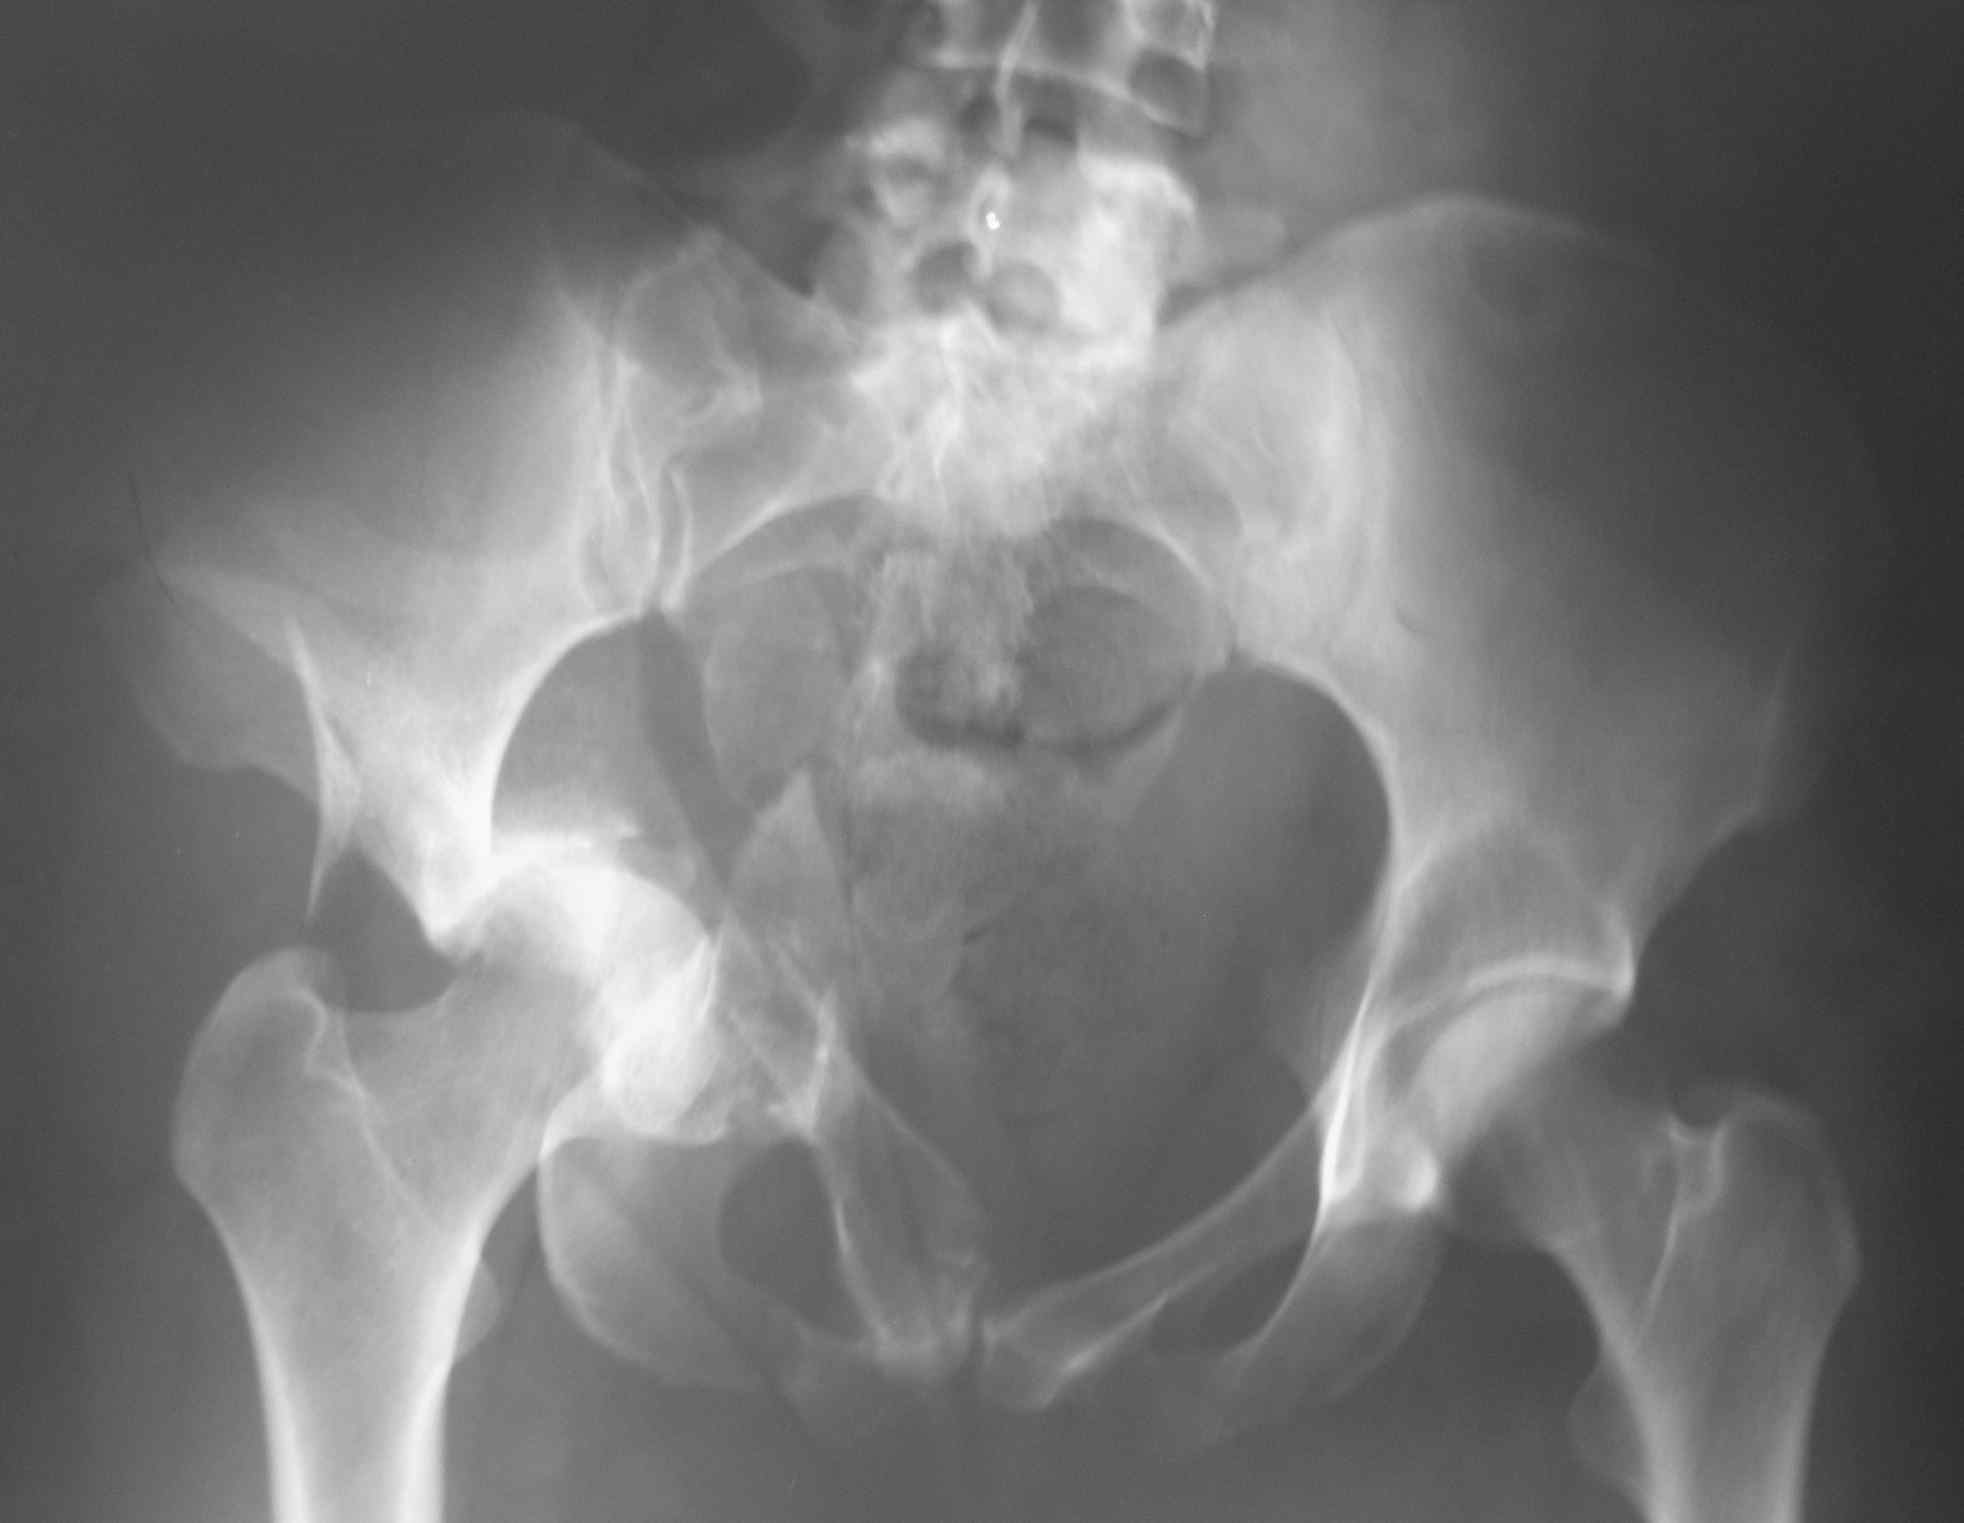

К сожалению, даже по представленным рентгенограммам видно, что ничего особенного после так называемого Вами вправления не изменилось. Если сделать КТ или МРТ картина будет ещё более удручающей. Прочитайте внимательнее пост Батала Алексеевича Шушании и прислушайтесь к его совету, потому, что время данной ситуации работает против пациента.

"перед выбором, либо идти на открытое вмешательство и восстанавливать переднюю колонну, либо продолжить вытяжение до консолидации переломов с последующей костной пластикой и эндопротезированием"

На основании одной проекции трудно определить к какому перелому вертлужной впадины относится данный перелом, тем более подсказать "подвздошно бедренный доступ, хотя можно и из бокового чрезвертельного" оперативный доступ. Нужны обязательные стандартные рентген снимки по Judet: прямой и косые снимки, из косых запирательный и подвздошные снимки ацетабулума. Рентген снимки и Компьютерную Томограмму лучше сделать после скелетнего вытяжения.